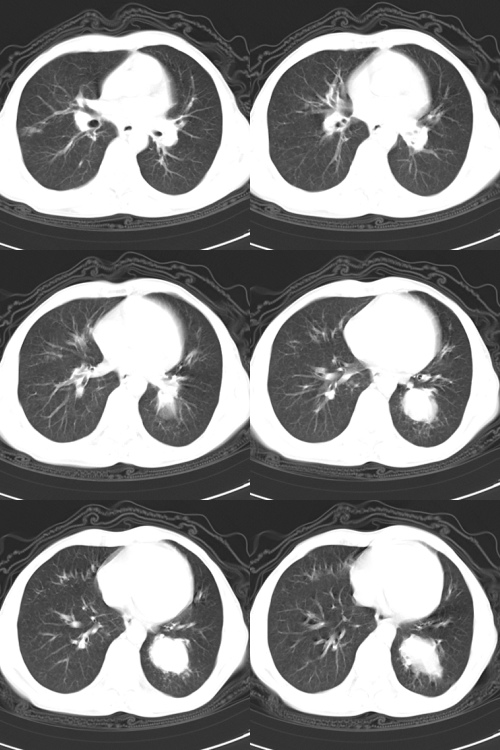

以下是引用zsl6918在2009-2-7 7:38:00的发言:[br]恶性度极高的肺癌,肺门及纵隔淋巴结转移。

以下是引用余辉在2009-2-7 8:29:00的发言:[br]考虑左下肺周围型肺癌伴肺门、纵隔淋巴转移及右肺转移